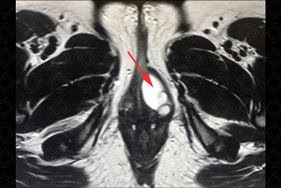

Texto alternativo para a imagem Figuras 1 e 2. Créditos: Dra. Elazir Mota - Rio de Janeiro/RJ

Descrição das figuras 1 e 2: Ressonância magnética da pelve; planos axial e sagital. Presença de cisto de glândula de Bartholin no introito vaginal esquerdo (setas vermelhas). Bx = bexiga, Ut = útero, Va = vagina, R = reto.

Exames de imagem: Na maioria dos casos, são identificados na ressonância magnética da pelve como lesão ovalada ou arredondada, com dimensões que variam de 3 a 5 cm, com sinal hiperintenso em T2 e hipointenso em T1, com discreta ou ausente captação parietal do meio de contraste. Diante de quadros infecciosos ou sangramento, pode haver hipersinal em T1 (figuras acima). Nos casos de cistos volumosos ou que crescem por alguma complicação, como abscesso, eles podem ser observados na tomografia computadorizada da pelve.